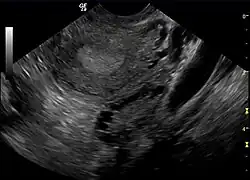

Ultrassonografia de ovário policístico.

A constatação, através de exame de ultrassom, de que os ovários apresentam múltiplos cistos, por si só, é insuficiente para caracterizar a ocorrência da síndrome, não sendo uma exigência absoluta para todas as definições conferidas à SOP.[9] Logo, a inexistência de cistos ovarianos não descaracteriza, necessariamente, a síndrome, podendo chegar-se ao diagnóstico de que determinada paciente sofre de SOP mediante outros critérios. Por isso, em janeiro de 2013, os Institutos Nacionais da Saúde dos EUA convocaram um painel independente para determinar se "síndrome dos ovários policísticos" seria o nome correto para designar tal distúrbio hormonal. Cientistas concluíram que o nome atual, que incide sobre um critério - cistos ovarianos - causa confusão e é uma barreira para obter-se progresso e atenção efetiva em prol da paciente.[10]

A constatação, através de exame de ultrassom, de que os ovários apresentam múltiplos cistos foi por muito tempo considerada a característica patognomônica para o diagnóstico da SOP, mas parece ser um achado inespecífico em aproximadamente 20% das mulheres que são assintomáticas[112]. Atualmente, considera-se o fato de apresentar ovários policísticos por si só insuficiente para diagnosticar síndrome. Também a inexistência de cistos ovarianos não descaracteriza, necessariamente, a ocorrência da síndrome[113][9]. Asso, nem todas as pacientes com SOP apresentam ovários policísticos e, da mesma forma, nem todas as mulheres com cistos ovarianos podem ser automaticamente diagnosticadas como portadoras da síndrome. Embora o exame de ultrassonografia pélvica seja uma importante ferramenta de diagnóstico, ela não é a única.[114]